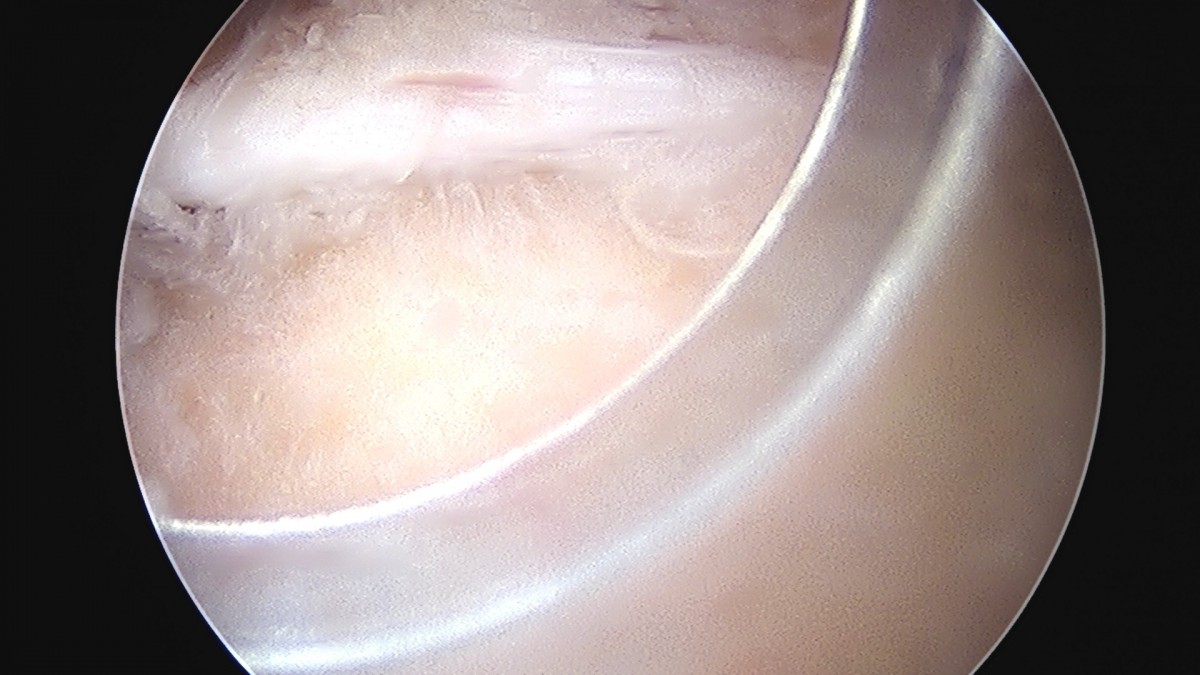

이재상원장님 어깨 견봉하 감압술 및 관절낭 이완술 류정O 환자

작성자 최고관리자 댓글 0건 조회 808회 작성일 25-09-16 15:30